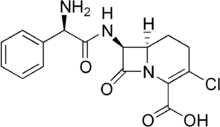

Loracarbef

Loracarbef is an antibiotic.[1] It is a carbacephem, but it is sometimes grouped together with the second-generation cephalosporin antibiotics. Loracarbef is a synthetic "carba" analog of cefaclor, and is more stable.

| Formula | C16H16ClN3O4 |

| Molar mass | 349.77 g·mol−1 |